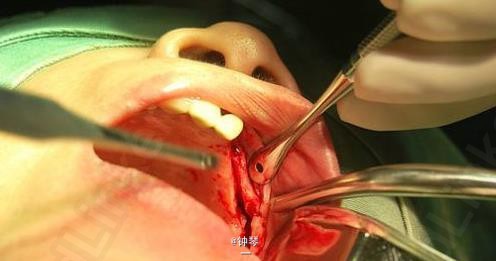

刀刃状牙槽嵴种植+钛网应用

患者,女,左上颌3、4、6要求种植。平素体质一般,否认高血压、糖尿病及心脏病史,否认肝炎、结核病史,无药物、食物过敏史,无外伤、手术及输血史。

左上3、4、6种植